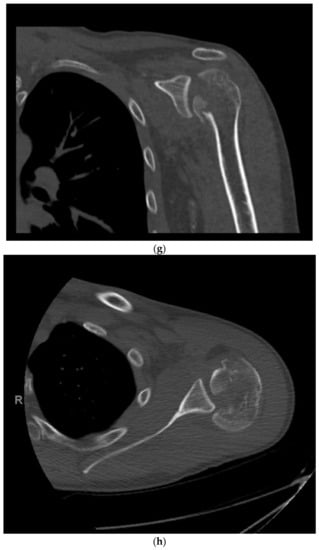

2. Classification

3. Clinical and Radiographic Assessment